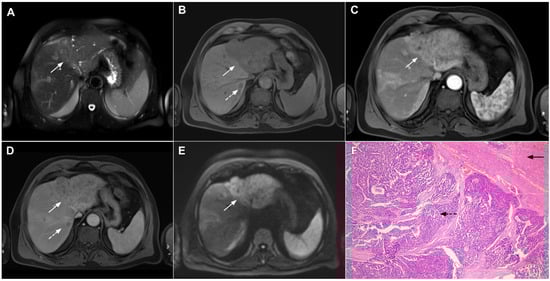

Scirrhous HCC is a rare variant of HCC characterized by rich intralesional fibrotic stroma with incidence of 4.6% among all HCC cases [76]. Scirrhous HCCs are usually seen in MRI scans as lobulated T1-weighted hypointense lesions with a heterogeneous signal intensity on T2-weighted images [77]. With regard to its vascular behavior, Kim et al. showed that the most common enhancement pattern was a peripheral rim-like enhancement in the arterial phase with a progressive central enhancement in the portal–venous and equilibrium phase, which is indistinguishable from mICC (Figure 17) [78]. Moreover, in previous studies washout was seen in only 19% of scirrhous HCC, in comparison to 99.7% of typical HCCs [78]. In addition, similarly to mICC, scirrhous HCC may also cause capsular retraction if it is subcapsular [79]. With regard to the targetoid appearance in the DWI and hepatobiliary phase, both mICC and scirhous HCC can display these imaging features [80]. Therefore, differentiation between scirrhous HCC and mICC represents a real diagnostic challenge, since both lesions have rich fibrous stroma, similar postcontrast behavior, and occur in cirrhotic livers [77]. Concerning different treatment strategies for these tumors, preoperative distinction is very important. In this context, the ancillary feature favoring the diagnosis of mICC include peripheral biliary dilatation, while the presence of a capsule suggests scirrhous HCC [77]. Moreover, the presence of part of the tumor enhancing avidly in the arterial phase favors the diagnosis of scirrhous HCC over mICC [80]. Additionally, Choi SY et al. have shown that mICC more frequently showed T2-weighted central brightness due to the presence of internal necrosis or mucin accumulation [79]. Nevertheless, if the lesion with imaging features of both scirrhous HCC and mICC is seen in the setting of chronic liver disease, according to the Liver Imaging Reporting and Data System (LI-RADS) it is characterized as LI-RADS M and further biopsy is required [81].

Figure 17.

Scirrhous hepatocellular carcinoma in a 68-year-old woman. The axial T2-weighted image (A) shows a moderately hyperintense subcapsular-located lesion in liver segments VI and V (arrow). Note also the capsular retraction. The tumor (arrow) is hypointense in the plain T1-weighted FS image (B), with ring enhancement in the arterial phase (C) and slight progressive central enhancement in the portal venous (D) and delayed phases (E). Hematoxylin and eosin (H&E) staining showed hepatocellular carcinoma (arrow) and normal liver parenchyma adjacent to the tumor (dashed arrow); original magnification ×40 (F).